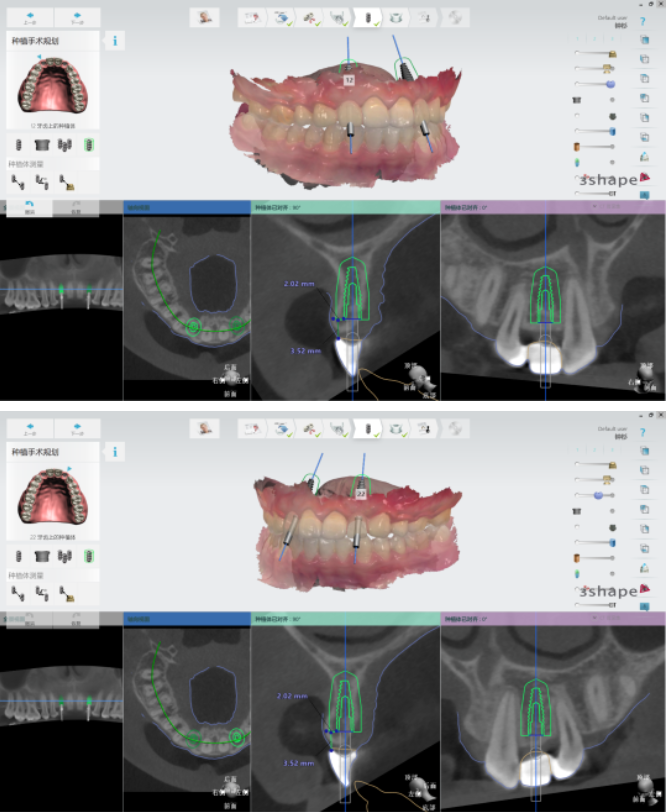

●根据最终的美学蜡型效果进行椅旁种植导板设计

●根据种植体位置,设计带翼预成临时冠

●15分钟快速打印种植导板